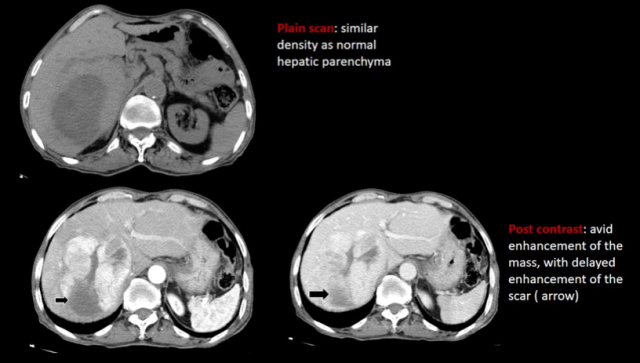

2. FNH

These can be seen de novo or in cancer survivors. Using hepatocyte specific contrast is a good way to diagnose FNH, as they will demonstrate uptake on the hepatobiliary phase images.

Healthy children Cancer survivors

-teenage girls -atypical features

-central T2 bright scar -smaller, multiple, no scar

-delayed enhancement of scar, -hyper on T2,prompt enhancement, then

-Rest shows prompt enhancement iso, intermediate restriction

with no washout